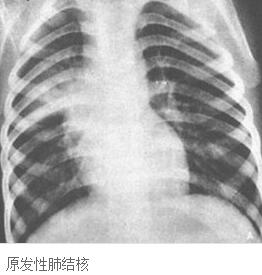

原发性$2型$3肺结核为原发结核感染$2即初次感染$3所引起的病症,包括原发综合征及胸内淋巴结结核。原发综合征在X线上呈现肺部原发病灶-引流淋巴管-肺门或纵隔淋巴结的结核性炎症的三者组合。有时肺部原发灶和引流淋巴管已吸收或不明显,X线上仅显示肺门或纵隔淋巴结肿大,称为支气管或气管淋巴结结核$2即胸内淋巴结结核$3。

原发性肺结核多见于儿童,青年和成人有时亦可见。原发综合征的肺部原发灶好发于上叶下部和下叶上部。初染结核时,由于早期特异性免疫力尚未形成,结核分枝杆菌沿引流淋巴管侵入肺门淋巴结,甚至有早期菌血症,形成播散病灶在其他脏器潜伏下来,成为日后肺外结核病的来源。大多数肺部原发病灶、淋巴管炎和淋巴结的炎症较轻并可自愈,少数由于机体免疫力明显低下或结核分枝杆菌毒力强、数量大及机体剧烈变态反应,发展为原发性肺结核病。